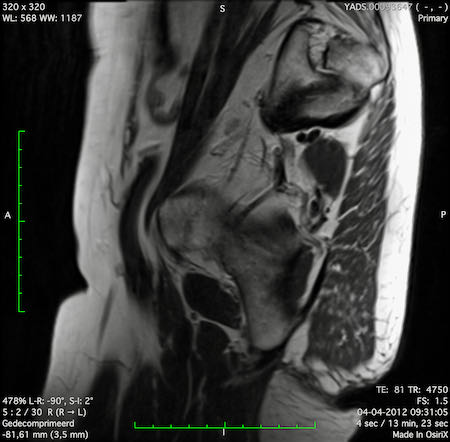

Đặc điểm MRI

- Thường khó xác định

- Thường biểu hiện nhưdày thành ruột lan tỏa, đoạn dài

- Kiểu tăng trưởng dưới niêm mạc, cho ra mộtHình ảnh “bia” (target)trên các hình ảnh cắt ngang

- Thâm nhiễm mỡ trực tràng lan tỏalà phổ biến

Hình ảnh

Các hình ảnh được cung cấp cho thấy ung thư biểu mô tế bào nhẫn với tình trạng dày lan tỏa thành trực tràng, hình ảnh bia bắn điển hình, và sự xâm lấn mỡ mạc treo trực tràng.